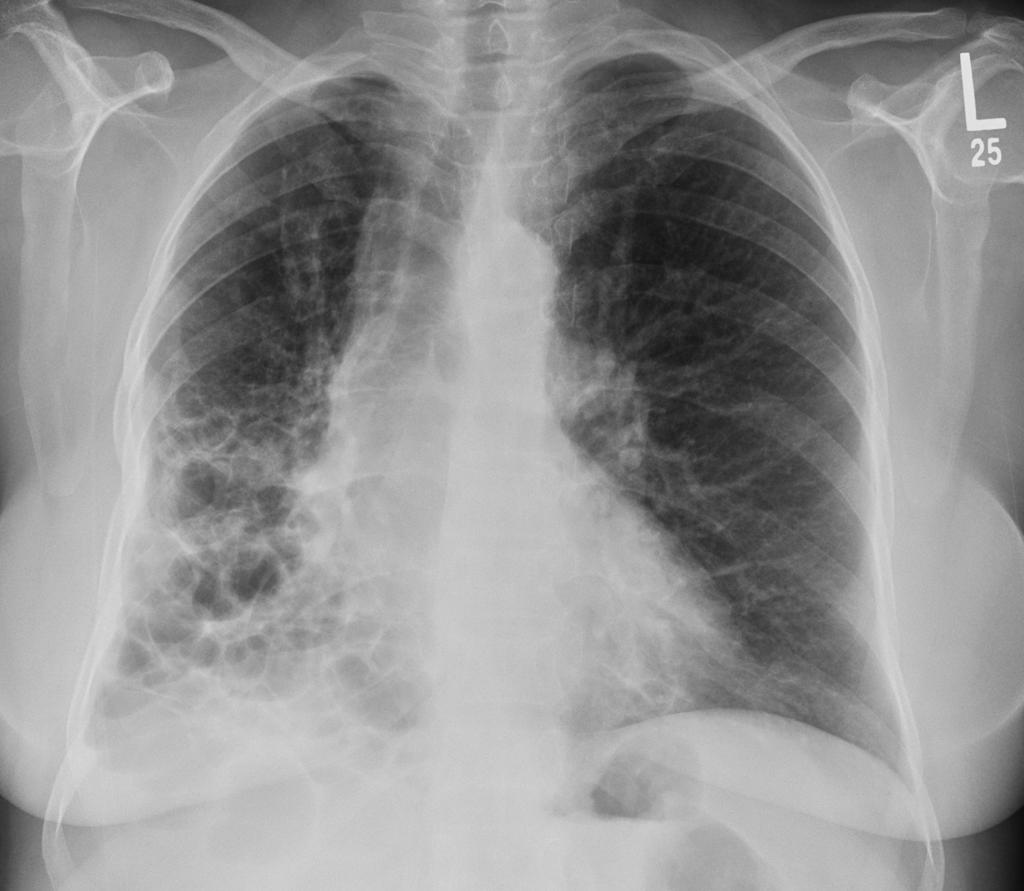

间质性肺疾病的常规医疗治疗方案

间质性肺疾病的治疗是一个系统工程,需要医生、患者和家属的共同努力。 抗纤维化药物帮我们控制疾病进展,免疫抑制治疗减轻炎症反应,氧疗和肺康复改善生活质量,肺移植...